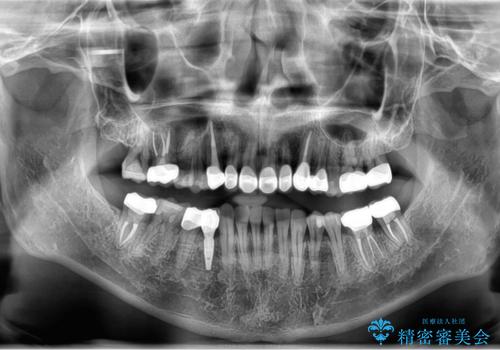

- 長年虫歯の治療を受け続けたことで銀歯・コンポジットレジン修復だらけになってしまい、今後の見た目や歯を大切にするためにセラミック治療矯正治療を希望され来院されました。

歯並びを整えたことで、歯ブラシのしやすさが向上し見た目も銀歯を全て除去したことで大きく改善して大変満足いただくことができました。